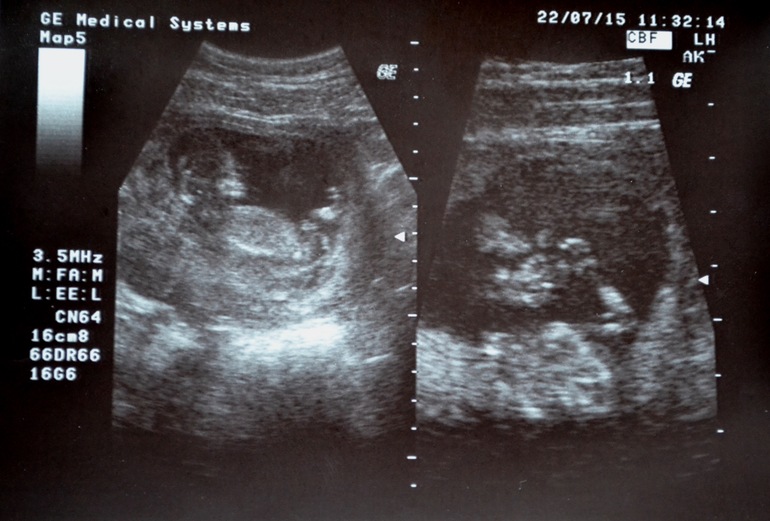

в итоге после разговора с акушер-гинекологом,явку поставила 22.07 и должна я была прийти с 1-м скрининговым УЗИ.Да и Узи у них нет,так что надо ехать отдельно к узистке,и понятное дело,что за деньги.Вообщем с 22-го я официально беременная и стою на учете в ЖК по ул.Богдана Хмельницкого)

По УЗИ у малыша все хорошо.Пол не увидели,потому что малыш лежал с согнутыми коленями и как не поворачивали датчик,не давал посмотреть.